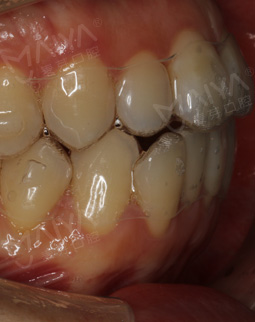

我的牙齿左侧上下植入支抗钉,这是为了更好的矫正,一点也不疼哦,所以说别看都是一样的牙套,不一样的医生做效果还是有区别的,所以选择去哪里的时候,还是要好好看一下效果和医生资质这些